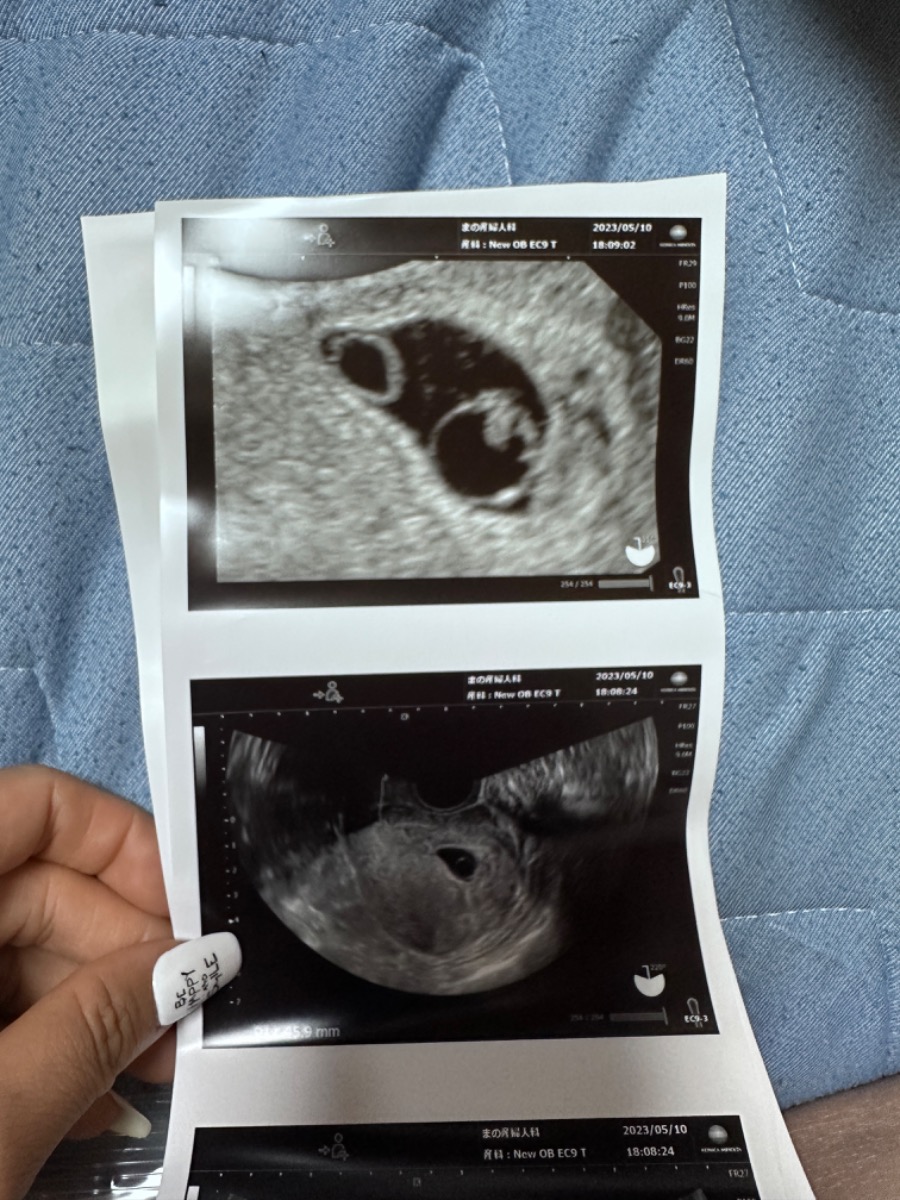

Em muốn hỏi là khi con được 6 tuần tuổi em siêu âm có thấy tim thai, nhưng hôm nay con được 8 tuần thì lại không thấy tim thai và bác sỹ có nói là thai không phát triển, khả năng lớn là sảy thai tự nhiên. Khi siêu âm, bác sũ còn thấy có 2 hình tròn trong tử cung, bác sỹ cũng chưa xác định được và hẹn em mấy ngày sau quay lại khám. Em thật sự rất lo lắng. Xin bác sỹ cho em lời khuyên ạ!

Thai nhi ở giai đoạn này còn rất nhỏ và tim thai chưa ổn định. Có những trường hợp tuần thứ 6 đã nghe thấy tim thai, nhưng cũng có trường hợp phải tuần thứ 8-10. Với trường hợp hiện tại, mom nên khám thai thêm tại một cơ sở y tế khác để so sánh kết quả giữa 2 bên. Sau khi khám, bác sĩ sẽ tư vấn cụ thể cho trường hợp của mom. Mom cũng lưu ý cần ăn uống đầy đủ, hạn chế vận động và tránh căng thẳng.